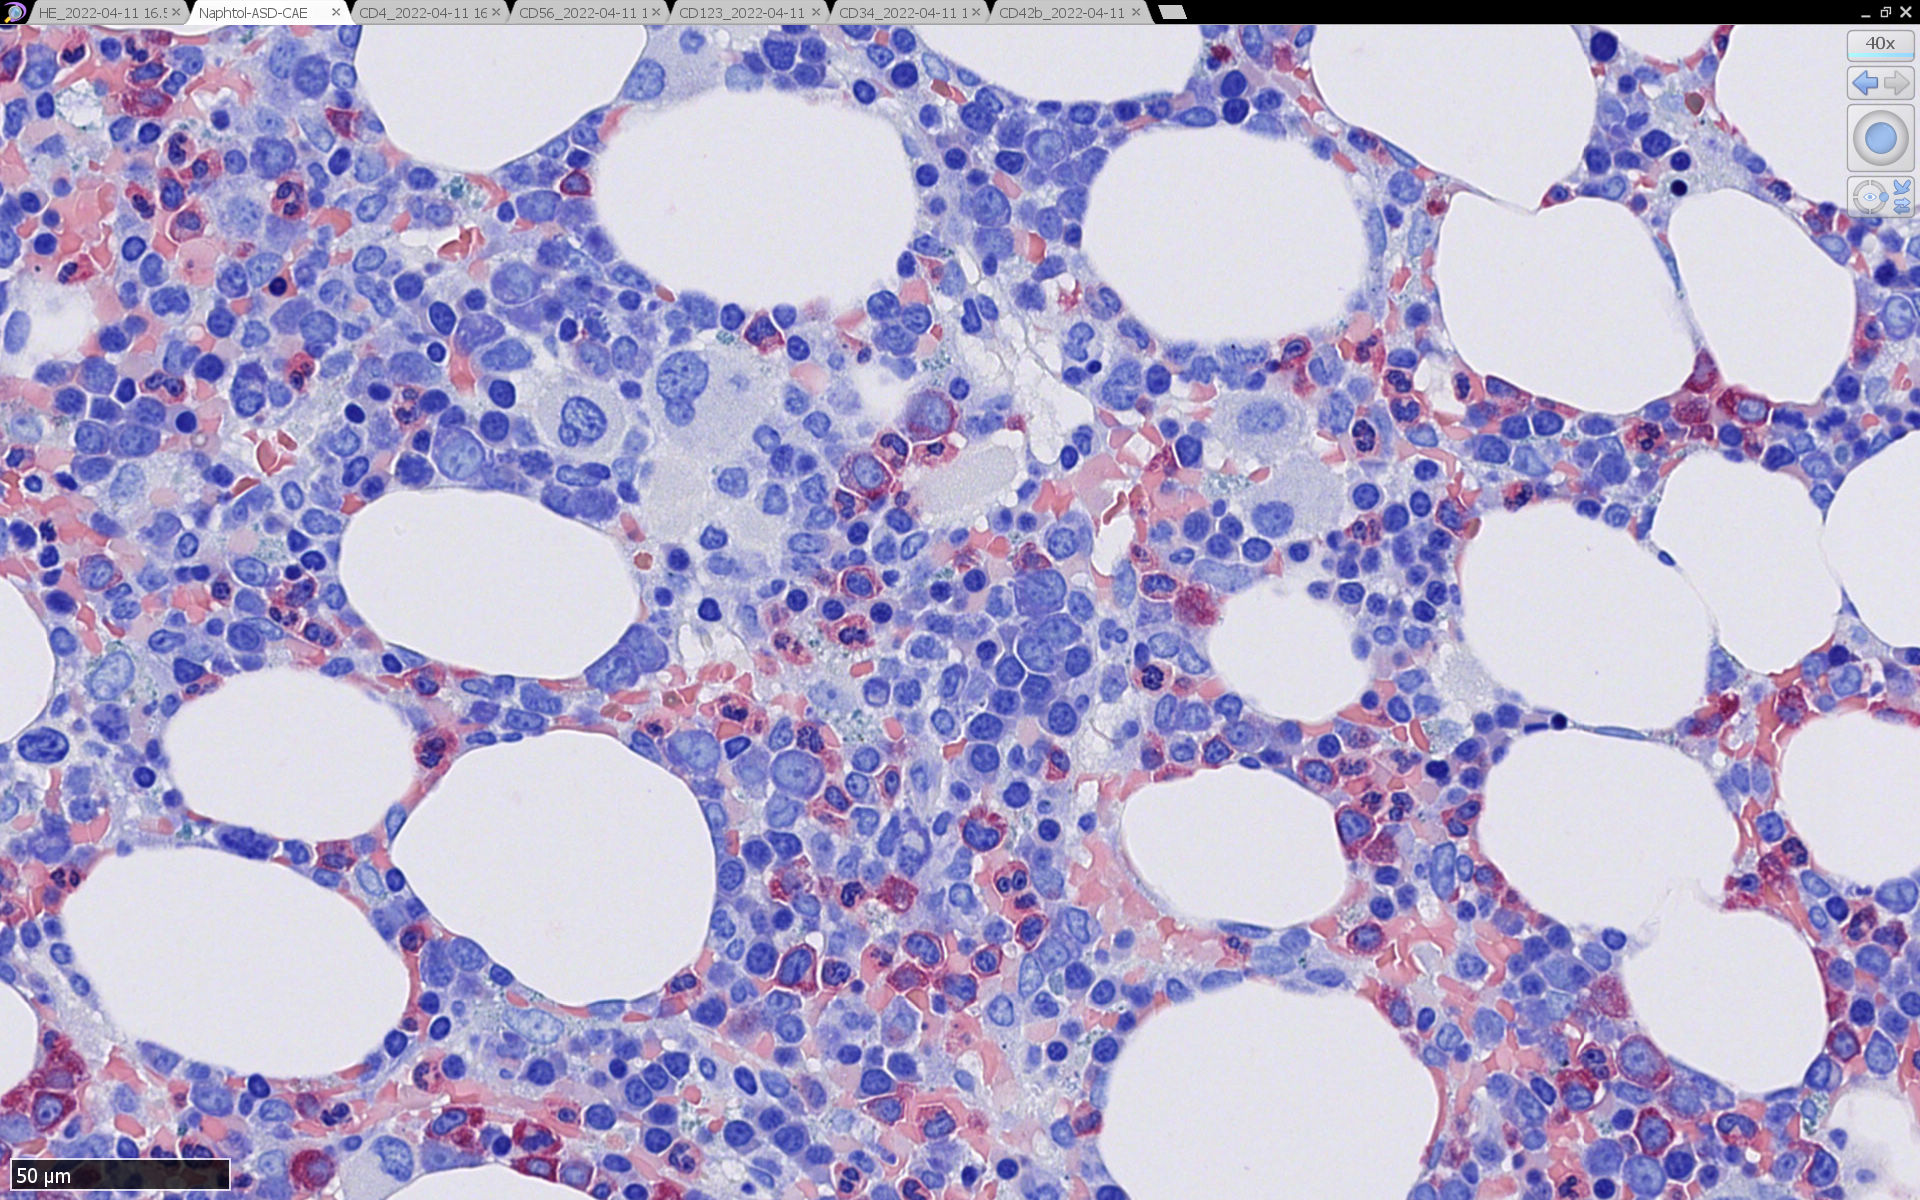

骨髄病理所見

HEでは腫瘍細胞の同定が難しい. 本症例は ASD-Giemsa染色を見ても, 腫瘍胞巣はよくわからなかった. 皮膚が先に診断がつき, 次いでBone marrowだったため, 免疫染色にすすめたが, Bone marrowが先だと診断に困ったかもしれない. 本例は, 骨髄がhypercellularで, dysplastic hematopoiesisがありMDSも疑われている.

免疫染色

CD4は染まりすぎの感がある(濃く染まる細胞はCD4+ T-cellかもしれない). CD56, CD123が陽性で可能性が高くなり, BPDCNの診断にはCD34は陰性であることが必要

TCF4、CD123、TCL1をconsultationにより染色していただき, 陽性を確認した. CD34-, lysozyme-, CD123(おいてある病院は少ないかも)をしらべて, BPDCN研究会あてconsultationをする流れでしょうか.